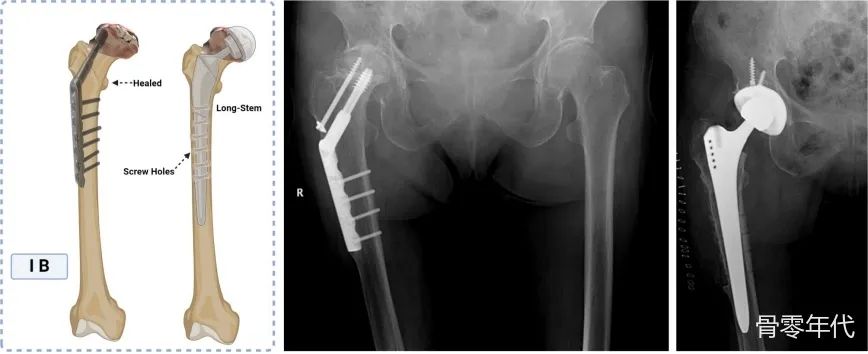

股骨粗隆间骨折是一种常见的骨科损伤,尤其是在老年人中。内固定是主要的治疗方法,有记录的失败率为3-12% 。对于临床医生来说,在失败后选择合适的治疗策略是一项艰巨的挑战。虽然髋关节置换术是内固定失败后的有效挽救手术,但髋关节置换术中股骨成分的选择仍然存在争议,尤其是在长柄和标准柄之间的选择。股骨粗隆间骨折内固定失败后,原始植入物的移除会在股骨近端留下螺丝孔,这些螺丝孔可能成为应力集中点,影响髋关节置换术中股骨假体的稳定性和术后功能恢复。因此,大多数骨科医生会考虑使用骨干贴合的长/翻修股骨柄,这有助于将应力从受损的近端区域转移到骨干更远的部分,提供更宽的骨接触区域并提高初始稳定性。然而,使用长柄会增加围手术期假体骨折的发生率。目前缺乏选择股骨假体的指南,这意味着不适当的选择可能会增加术中和术后并发症的风险,尤其是假体周围骨折和无菌性松动,这些并发症比初次髋关节置换术更常见。